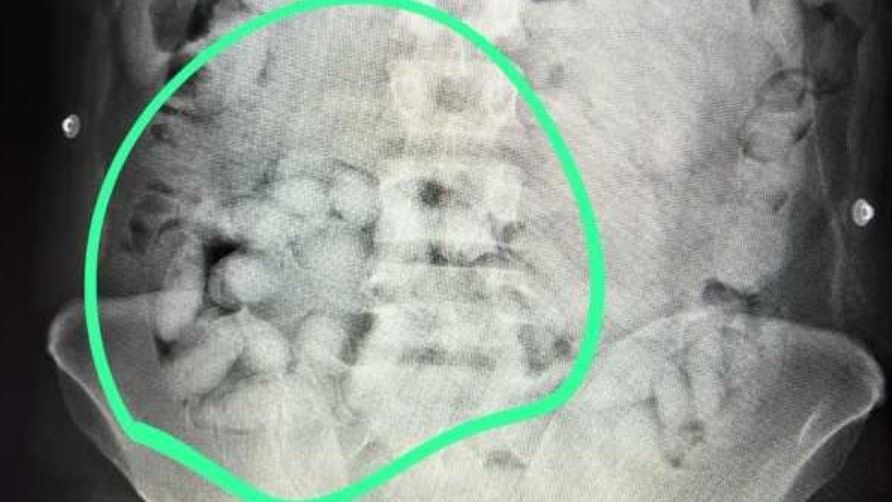

A közlemény szerint a fiatalember ragasztószalaggal a lábszárához erősített két csomag drogot. Emellett az utasszkenneres átvilágításakor a rendőrök felfedeztek összesen 350 gramm, egyelőre ismeretlen eredetű anyagot is, amit lenyelve próbált becsempészni Romániába. Emiatt kórházba szállították, ahol összesen 62 kapszulát távolítottak el a szervezetéből.